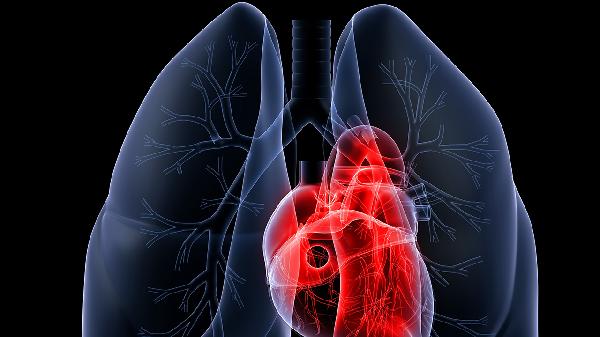

肺部二氧化碳过高怎么治疗

肺部二氧化碳过高可通过氧疗、药物治疗、机械通气、调整生活方式、治疗原发病等方式改善。肺部二氧化碳过高可能与慢性阻塞性肺疾病、呼吸肌无力、中枢性呼吸抑制、严重肺炎、胸廓畸形等因素有关。